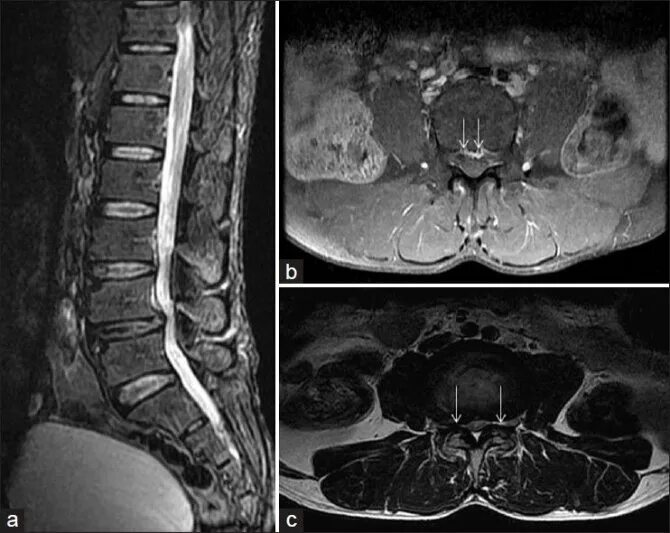

Расшифровка снимков